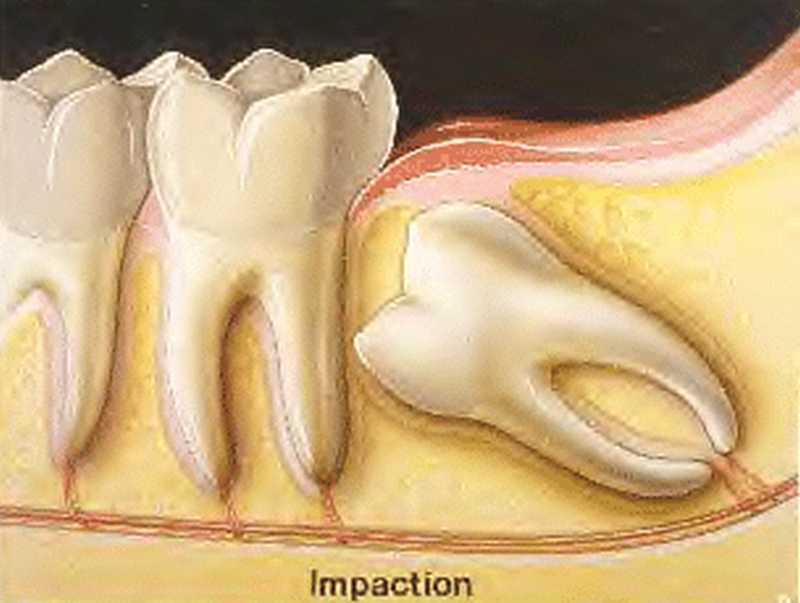

Inicio Especialidades Cirurgia